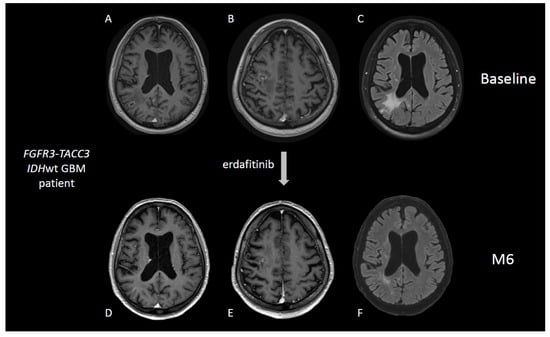

5.3. Inhibition of FGFR3-TACC3 Gene Fusions and Activating Mutations of FGFR1 Gene

- Di Stefano, A.L.; Picca, A.; Saragoussi, E.; Bielle, F.; Ducray, F.; Villa, C.; Eoli, M.; Paterra, R.; Bellu, L.; Mathon, B.; et al. Clinical, Molecular, and Radiomic Profile of Gliomas with FGFR3-TACC3 Fusions. Neuro-Oncology 2020, 22, 1614–1624. [Google Scholar] [CrossRef]

- Di Stefano, A.L.; Fucci, A.; Frattini, V.; Labussiere, M.; Mokhtari, K.; Zoppoli, P.; Marie, Y.; Bruno, A.; Boisselier, B.; Giry, M.; et al. Detection, Characterization, and Inhibition of FGFR-TACC Fusions in IDH Wild-Type Glioma. Clin. Cancer Res. 2015, 21, 3307–3317. [Google Scholar] [CrossRef] [Green Version]